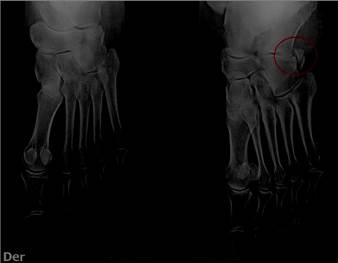

Figura 1 Imagen radiográfica vistas anteroposterior y oblicua de pie izquierdo, paciente femenino de 66 años, presencia de Os Peroneum. (círculo rojo).